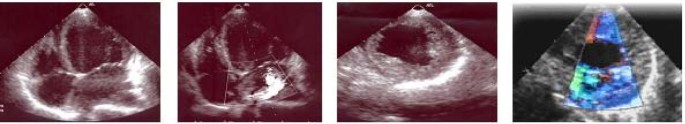

A new echocardiogram (Figure 3) demonstrated exuberant thickening and trabeculation of the lateral and posterior walls of the apical half of the left ventricle with two distinct myocardial layers: a normal compact (C) epicardium and a thickened non-compact (NC) endocardium. The ratio between NC endocardium and C epicardium = 2,2 (measured at end systole in parasternal short axis view). Left ventricle cavity was dilated and presented diffuse hypokinesis and an ejection fraction of 38%. No additional abnormalities were found. These findings were consistent with the diagnosis of IVNC.

Echocardiogram suggesting IVNC. Exuberant thickening and trabeculation of left ventricle(LV) apical wall. Ratio between non-compacted endocardium and compacted epicardium = 13/6 (measured at end systole in parasternal short axis view). Dilated LV, diffuse hypokinesis, ejection fraction = 38%. Colour Doppler image showing recesses supplied by intraventricular blood.

IVNC is generally detected by means of bidimensional echocardiography with Doppler, which is considered the reference method for the diagnosis [5, 7, 8]. Echocardiographic findings consist on a two-layered myocardium with a thin (compacted) epicardium, a thick (non-compacted) endocardium composed of a trabecular meshwork, numerous proeminent trabeculae and deep intertrabecular recesses in continuity with ventricular cavity. Predominant segmental locations occur in the mid lateral, apical and inferior walls. Hypokinetic movements occur either in the affected areas or in the surrounding normal segments [7]. No other abnormalities should be found [2, 7–9].

Several diagnostic criteria have been proposed in the literature [2, 7–9, 12, 13]. In this clinical case diagnosis was primarly established by echocardiogram according to the criteria defined by Jenni and colleagues [7]. According to these authors diagnosis is based on the detection of 2 myocardial layers, with a normal compact (C) epicardium and a thickened non-compact (NC) endocardium. They propose a quantitative evaluation by determining the ratio between the 2 layers NC/C ≥ 2, measured at end systole in parasternal short axis view, to establishe diagnosis [7]. This allows differentiation of the trabeculations of IVNC from that observed with DCM and HCM [7].